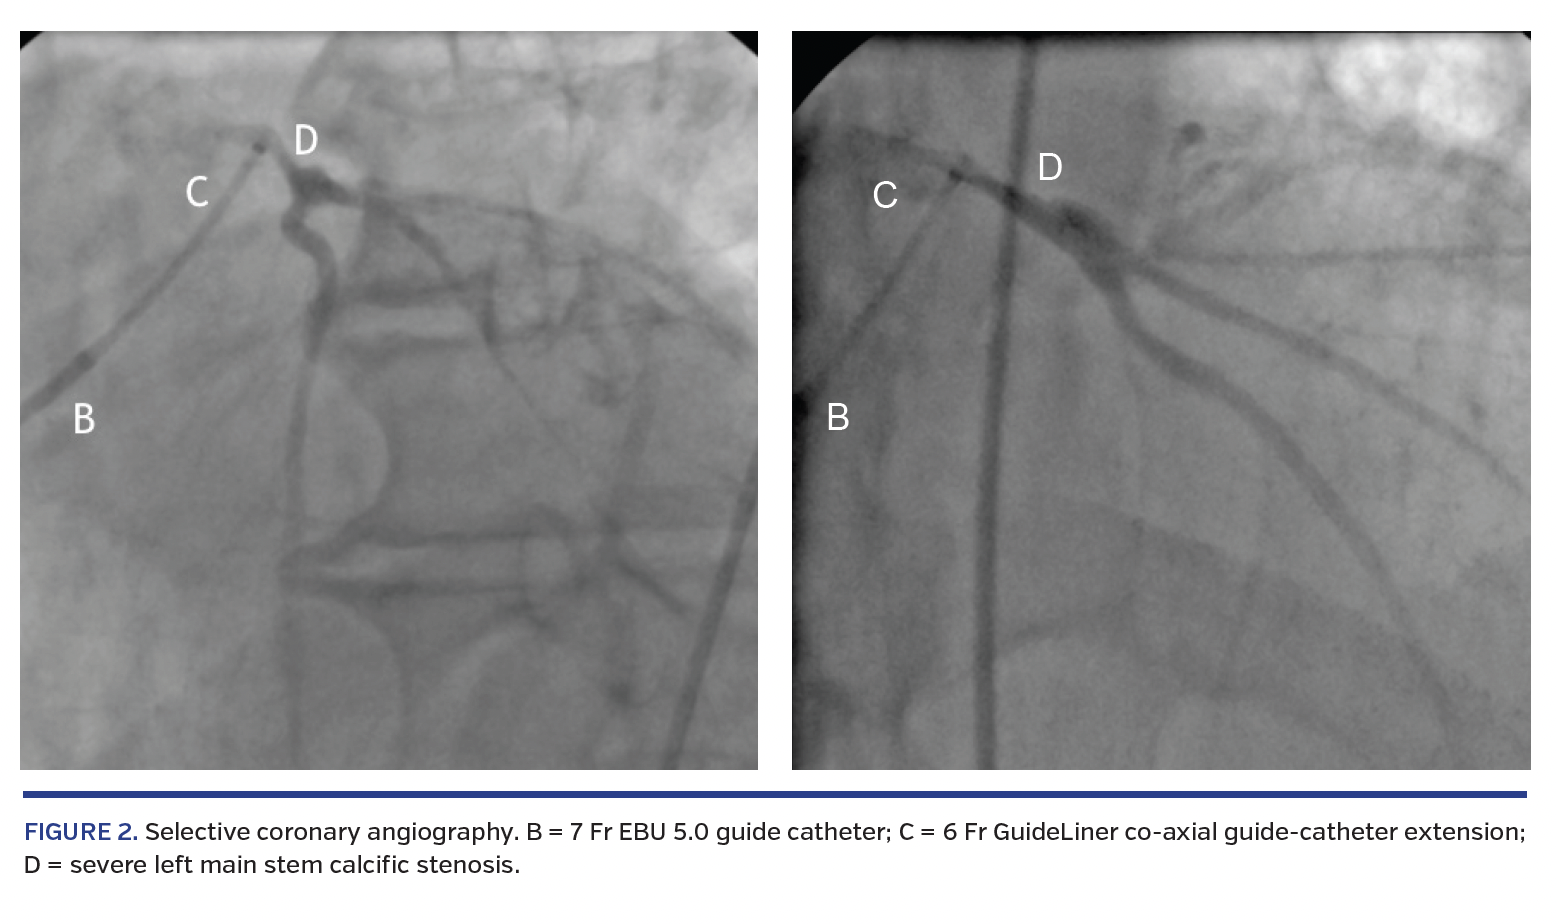

Repeat coronary angiography was performed at our center. Sub-selective coronary angiography of the RCA was possible with a 7 Fr Amplatz Left 3.0 guide catheter demonstrating unobstructive disease. Selective coronary angiography of the LMS was achieved with telescopic extension of a 7 Fr EBU 5.0 guide catheter with a 6 Fr GuideLiner coaxial guide-catheter extension (Vascular Solutions) (Figure 2), demonstrating severe LMS calcific stenosis and atheromatous but unobstructed LAD and LCX arteries. The patient subsequently underwent successful aortic root replacement with a tissue aortic valve, and concurrent coronary artery bypass graft surgery from the aorta to the LAD. He stepped down from cardiothoracic intensive care within 24 hours postoperatively.